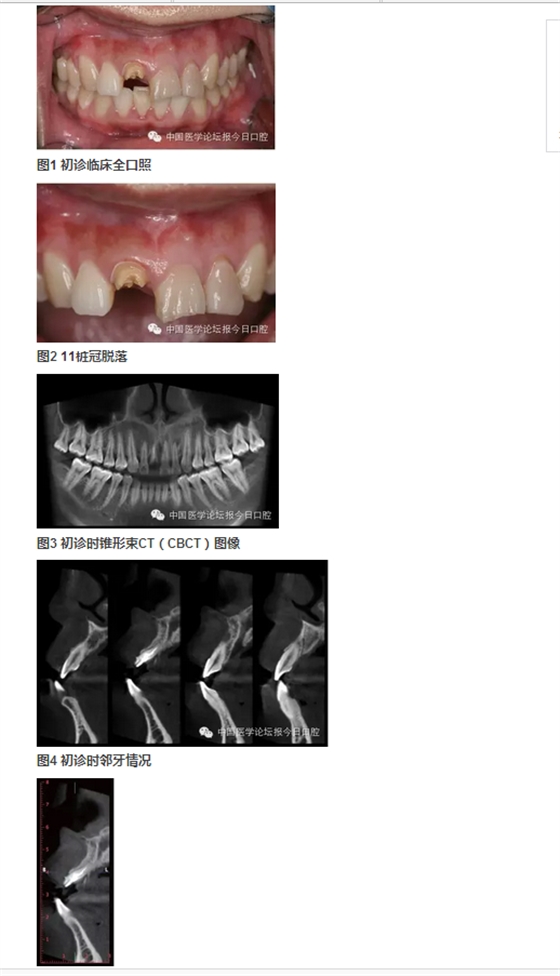

北京大學(xué)口腔醫(yī)院種植科 在唇側(cè)和舌側(cè)牙槽突骨板骨折的病例中,唇/舌側(cè)牙槽突發(fā)生相應(yīng)的骨吸收。長期的臨床經(jīng)驗(yàn)告訴我們,唇側(cè)和舌側(cè)骨板的低位骨折,任其常規(guī)牙槽窩愈合,會(huì)導(dǎo)致三維方向的骨缺損。根據(jù)ITI機(jī)構(gòu)的SCA分類,伴有垂直和水平骨缺損的病例,則是復(fù)雜和高難度病例,美學(xué)風(fēng)險(xiǎn)極大。即刻種植無法預(yù)防和避免骨吸收。 在本病例中,我們采用符合富血小板纖維蛋白(PRF)技術(shù)的牙槽窩位點(diǎn)保存技術(shù),最大限度保存局部骨量。以及采用輪廓擴(kuò)增的引導(dǎo)骨再生(GBR)技術(shù)同期種植重建了種植位點(diǎn)的三維骨結(jié)構(gòu),通過暫時(shí)冠誘導(dǎo)穿齦輪廓和牙齦乳頭形態(tài),最終獲得患者滿意的美學(xué)修復(fù)。 女性,27歲。以“右上前牙樁冠修復(fù)11年,脫落1周”為主訴前來就診。 11年前,患者前牙外傷,于當(dāng)?shù)蒯t(yī)院行11、21、22根管治療及11樁冠修復(fù)。1周前11樁冠脫落,于多家醫(yī)院修復(fù)科就診,以“11牙槽突骨折”的診斷,無法保留11殘根,建議拔除,而前來就診。 既往體健,否認(rèn)系統(tǒng)性疾病史及藥物過敏史。 臨床檢查可見11殘根,21、22牙冠變色。前牙區(qū)咬合略緊,Ⅱ度深覆牙合。CBCT示上頜右側(cè)中切牙頰側(cè)根頸1/3骨板折裂。21、22牙冠變色。前牙區(qū)咬合略緊,Ⅱ度深覆牙合。CBCT示上頜右側(cè)中切牙頰側(cè)根頸1/3骨板折裂。21、22根尖病變,前牙區(qū)牙槽突根方骨量不足。 圖6 舌側(cè)骨缺損的3D重建 診斷 ①右上中切牙牙槽突骨折(?);② 左上中切牙、側(cè)切牙慢性根尖炎;③Ⅱ度深覆牙合。 病例特點(diǎn)與難點(diǎn) ①樁冠修復(fù)失敗后的三維骨缺損(頰/舌側(cè)骨板折裂、牙槽骨根方骨量不足);②年輕女性,美學(xué)要求較高;③ 鄰牙根尖周病變;④輕度深覆牙合,咬合略緊。上頜骨基底骨骨量不足,正畸醫(yī)師不建議矯正。 治療設(shè)計(jì) ①正畸會(huì)診,希望下前牙下壓,改善咬合緊,深覆牙合;② 左上中切牙、側(cè)切牙根管治療,必要時(shí)行根尖手術(shù),貼面修復(fù)改善美觀;③ 右上中切牙牙槽窩位點(diǎn)保存,根據(jù)牙槽嵴骨量保持情況,確定二期種植和植骨以及必要的軟組織整理和塑形。 1.正畸科醫(yī)師會(huì)診,因患者上頜牙槽骨基底骨骨量不足,多數(shù)牙齒唇側(cè)骨板不足或缺失,正畸風(fēng)險(xiǎn)大而建議放棄正畸治療。 2.因無法進(jìn)行正畸治療,故需要合理的種植位點(diǎn)和修復(fù)方式,以適應(yīng)患者的咬合情況。 3.牙體牙髓科醫(yī)師會(huì)診,進(jìn)行左上中切牙、側(cè)切牙根管治療后隨訪,根據(jù)愈合情況決定是否進(jìn)行根尖手術(shù)。 4.右上中切牙牙槽窩位點(diǎn)保存+富血小板纖維蛋白(PRF)技術(shù)。 5.6個(gè)月后行種植+引導(dǎo)骨再生(GBR)。 6.愈合4個(gè)月后,行軟組織增量和塑形,擇期永久修復(fù)。 7.愈合期內(nèi),以馬里蘭橋或壓膜過渡義齒臨時(shí)修復(fù)。 8.左上中切牙、側(cè)切牙貼面修復(fù)改善美觀。 ④ Bio-Oss®; ⑤ NobelProcera全瓷修復(fù)。 ①左上中切牙、側(cè)切牙經(jīng)根管治療后,根尖病變隨訪期內(nèi)縮小并逐漸消失,避免了進(jìn)一步的根尖手術(shù); ②右上中切牙牙槽窩位點(diǎn)保存+PRF技術(shù)治療,避免了牙槽嵴可能發(fā)生的三維方向骨缺損,極大限度保持和原位重建局部骨量; ③在種植位點(diǎn)軟組織和硬組織無缺損的情況下,在較佳的三維位點(diǎn)植入種植體,同期GBR行輪廓擴(kuò)增的骨增量技術(shù),應(yīng)用低替代率的骨代用品,獲得較好的長期穩(wěn)定性; ④左上中切牙、側(cè)切牙貼面修復(fù)美學(xué)效果較好; ⑤經(jīng)過治療和口腔健康宣教,患者口腔衛(wèi)生情況得到較大提高; ⑥在妊娠期齦炎時(shí),修復(fù)體和天然牙周圍的牙齦不同程度受累,但是種植修復(fù)體周圍牙齦穩(wěn)定,點(diǎn)彩未消失。 ①適宜技術(shù)的選擇,序列治療計(jì)劃的選擇、制定和執(zhí)行,在口腔種植美學(xué)修復(fù)中具有很重要的意義。 ②錐形束CT在口腔種植的臨床診斷和治療設(shè)計(jì)中起到了重要的作用。 ③符合PRF技術(shù)的牙槽窩位點(diǎn)保存技術(shù),充分應(yīng)用了PRF技術(shù)在軟組織愈合上的優(yōu)勢。經(jīng)PRF膜技術(shù)在封閉牙槽窩的同時(shí),促進(jìn)牙齦上皮的生長。在局部軟組織愈合的條件下,進(jìn)一步促進(jìn)骨組織的生長。從而最大限度地保存了種植位點(diǎn)的骨量。 ④輪廓擴(kuò)增的GBR技術(shù)使用過增量的植骨,自體骨+低替代率骨代用品+可吸收膠原膜+可靠的膜釘固定技術(shù),從而重建出種植體周圍健康的軟硬組織形態(tài)。 ⑤暫時(shí)冠技術(shù),對于穿齦輪廓的誘導(dǎo)和成型具有良好效果。 ⑥經(jīng)過序列治療的種植修復(fù),具有較好的美學(xué)效果和長期穩(wěn)定性,在妊娠期齦炎,隨著激素水平的變化,上頜前部美學(xué)區(qū)天然牙和修復(fù)體周圍出現(xiàn)不同程度的水腫,但是種植體周圍牙周健康,點(diǎn)彩存在。 周磊教授: 位點(diǎn)保存技術(shù)包含軟組織與硬組織的保存。通常牙缺失后牙槽嵴在1個(gè)月之內(nèi)軟組織修復(fù)重建,而硬組織尚未明顯吸收。但這個(gè)時(shí)期如不給予人為干預(yù),軟組織修復(fù)常陷于牙槽窩內(nèi),形成凹陷,不利于植入種植體后的軟組織成形及傷口的關(guān)閉。 國際口腔種植學(xué)會(huì)前任主席Buser介紹的完整的位點(diǎn)保存技術(shù)是:拔牙后植入膠原骨,1個(gè)月以后軟組織重建修復(fù)形成較為豐滿的外形,然后再切開,將牙槽窩內(nèi)殘存的膠原骨刮除,植入骨粉3~6個(gè)月后再行種植體植入,這樣確保了拔牙位點(diǎn)豐滿的外形。 軟硬組織修復(fù)重建分兩步進(jìn)行的原因是:膠原骨有較好的細(xì)胞趨化特性,可促進(jìn)鄰近的牙齦組織生長進(jìn)入,但膠原骨會(huì)較快吸收,在其完成誘導(dǎo)軟組織生長任務(wù)后,更換為吸收速率較低的充填材料(Bio-Oss小牛無機(jī)骨粉)更利于硬組織的修復(fù)重建及重建后穩(wěn)定性;如直接選用吸收速率較低的充填材料一次完成位點(diǎn)保存,由于軟組織量不足,在牙槽嵴頂部常難維持骨粉的位置。 該病例屬于軟組織的位點(diǎn)保存,可看到,二期手術(shù)時(shí),軟組織已較豐富,但翻開后可見硬組織,既無明顯的重建也無明顯的吸收,在植入種植體后,可將傷口理想地關(guān)閉。